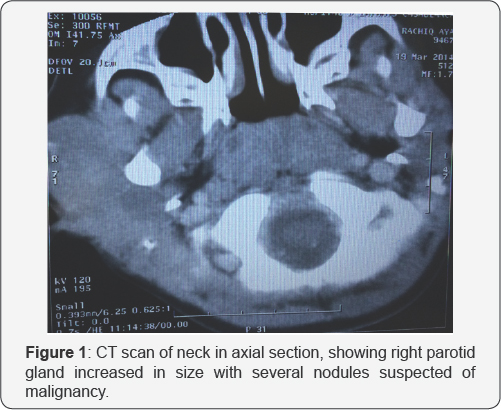

It is about a 4 years old child, operated one year ago for retinoblastoma of the right eye by enucleation followed by sessions of chemotherapy. He presented 3 months before admission in our department a right parotid mass progressively increasing in volume. This mass was hard and fixed, measuring 5cm of major axis, without palpable lymph nodes. A cervical CT scan showed an enlarged right parotid gland, with several nodules suspected of malignancy, and infra-centimetric lymph nodes on the right side of the neck (Figure 1). A total parotidectomy with preservation of the facial nerve with homolateral cervical lymph node dissection was performed. The histology found an undifferentiated nodule in the parotid gland with metastatic lymph nodes.